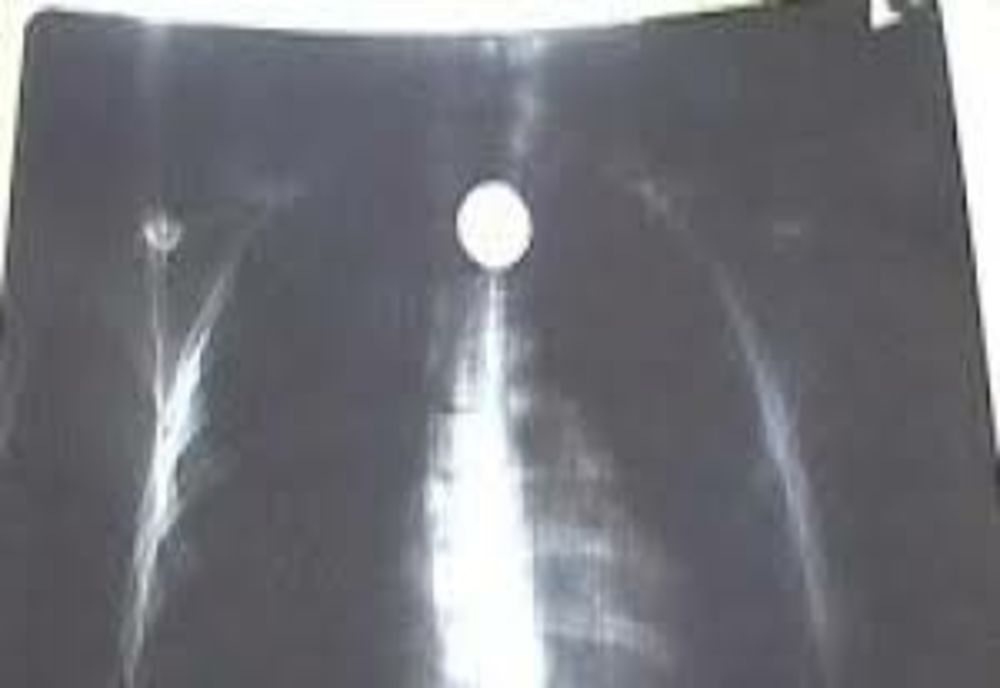

Un băiețel în vârstă de 3 ani, din comuna Albești, a ajuns la spital după ce înghițit o monedă de 50 bani. Părinții au observat că are dificultăți în respirație și au încercat să scoată obiectul, dar nu au reușit.

Îngrijorat de starea micuțului, tatăl a cerut ajutor la 112. La fața locului a fost direcționat cel mai apropiat echipaj al Serviciului Județean de Ambulanță. În același timp a fost trimisă în întâmpinarea echipajului SAJ și ambulanța de terapie intensiva mobila SMURD. La sosirea primului medical, copilul era conștient. La Stăuceni, echipajului Serviciului Județean de Ambulanta s- a alăturat medicul de pe SMURD - TIM, care a monitorizat starea parientului pe parcursul transportului la Secția de Pediatrie a Spitalului Județean de Urgență Mavromati Botoşani. Copilul a ajuns la spital conștient și stabil hemodinamic.